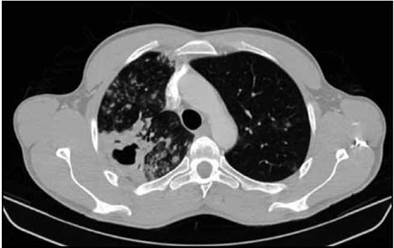

Posteriormente se obtuvo dos de tres baciloscopias positivas para bacilos ácido alcohol resistente en dos cruces (++ BAAR). La serología de anticuerpos para virus de inmunodeficiencia humana fue negativa. Se inició tratamiento antituberculoso estándar a base de tetraconjugado (rifampicina + isoniacida + pirazinamida + etambutol) ajustado al peso. Por progresión a hemoptisis no masiva, se realizó tomografía de tórax de alta resolución, documentándose múltiples densidades parcheadas, difusas comprometiendo ambos campos pulmonares, pero con mayor compromiso del pulmón derecho. También se anotó la presencia de cavitación en el lóbulo superior derecho, de 25 x 22 mm de diámetro con área de consolidación pericavitaria (Figura 1).